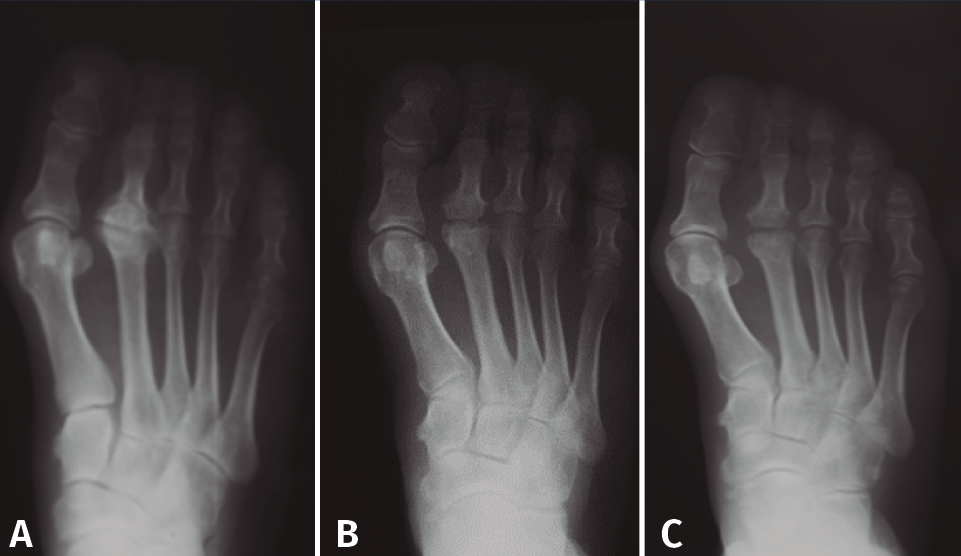

Figura 5. Tratamiento conservador. Paciente tratada con plantilla de descarga. A: imágenes al inicio del tratamiento; B: 2 años más tarde, mínima afectación articular.

En las fases iniciales (estadios 1 y 2 de Smillie) en las que, tal como se ha comentado, las molestias del paciente son inexistentes o leves, están indicadas las plantillas ortopédicas de descarga de la cabeza metatarsal afecta, los antiinflamatorios no esteroideos (AINE) y la electroterapia antiinflamatoria durante la crisis de dolor. Se recomienda al paciente disminuir la práctica deportiva de impacto(11,17). Con ello se consigue que, cuando se finaliza la fase de reparación, la deformidad sea la menor posible (Figura 5).

Figura 10. Queilectomía. Resultados a largo plazo. A: preoperación; B: postoperatorio inmediato; C: 17 años postoperación.